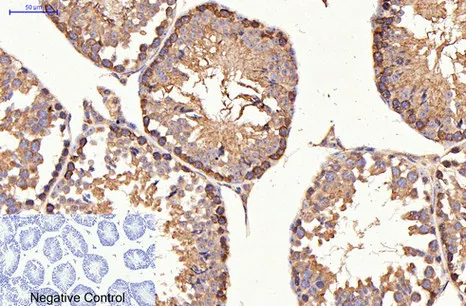

HER2(11H9)Mouse Monoclonal Antibody

Cat: AMM11986

Size1:50μL Price1:$118

Size2:100μL Price2:$220

Size3:200μL Price3:$380

Application:WB,IF-P,IF-F,ICC/IF,IHC-P

Reactivity:Human,Mouse,Rat

Conjugate:Unconjugated

Optional conjugates: Biotin, FITC (free of charge). See other 26 conjugates.

Gene Name:ERBB2